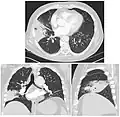

El diagnóstico se realiza, fundamentalmente y dentro de un contexto clínico, por la radiografía de tórax.

TAC del mismo caso.